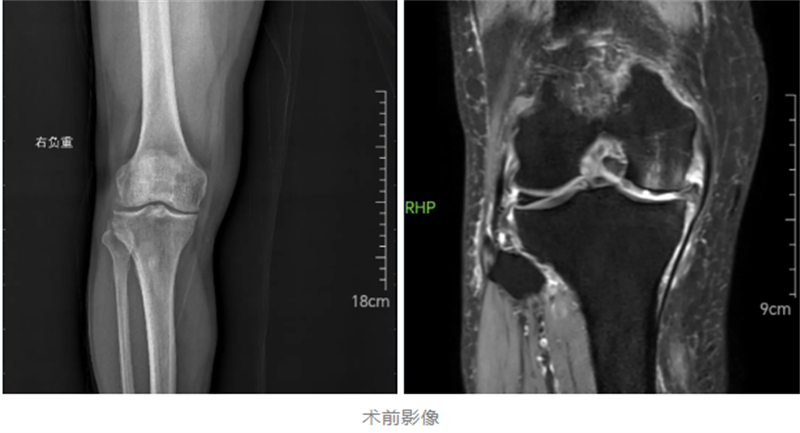

經(jīng)過詳細(xì)檢查,關(guān)節(jié)骨病科副主任韋健博士診斷楊先生為重度骨關(guān)節(jié)炎。鑒于患者疼痛集中于膝關(guān)節(jié)前內(nèi)側(cè),建議采用損傷小、恢復(fù)快的膝關(guān)節(jié)單髁置換術(shù)。“單髁置換就像給磨損的鞋底更換前掌,通過替換病變軟骨面,更多保留正常關(guān)節(jié)組織。” 韋健博士解釋道。